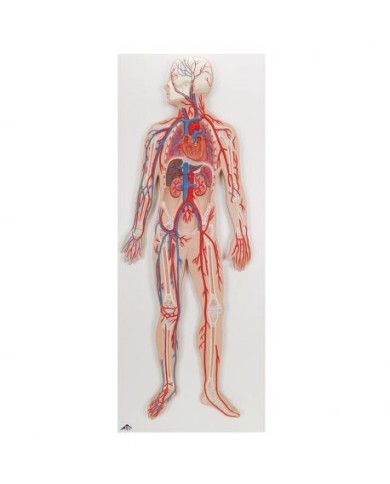

Kit composto da 3 modelli

Su tavola, con supporto e istruzioni per l'insegnamento. Con colorante rosso e siringa di riempimento.